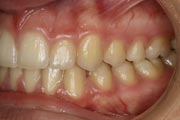

Crowding

Before